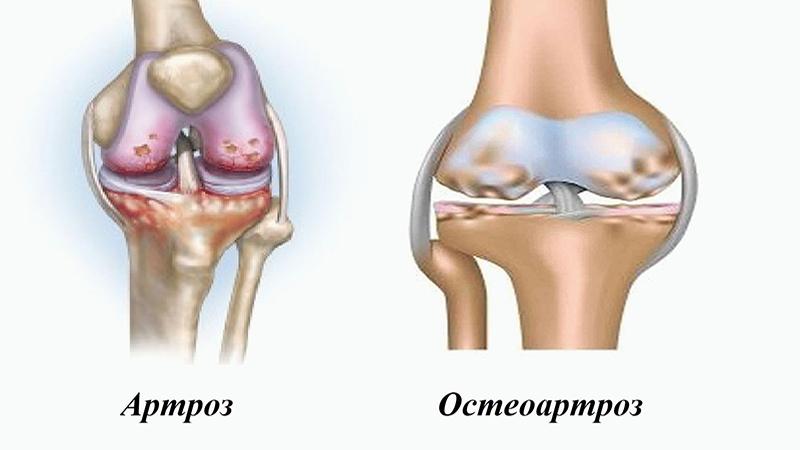

Врачи подчеркивают, что артрит и артроз — это два различных заболевания, хотя оба затрагивают суставы. Артрит представляет собой воспалительное заболевание, которое может быть вызвано инфекцией, аутоиммунными процессами или травмами. Он часто сопровождается отеком, покраснением и болезненностью суставов, а также может затрагивать другие органы. В отличие от артрита, артроз — это дегенеративное заболевание, связанное с износом хрящевой ткани суставов. Симптомы артроза включают боль и ограничение подвижности, но воспалительных процессов, как правило, нет. Врачи рекомендуют различать эти состояния для назначения адекватного лечения, так как подходы к терапии могут значительно различаться.

Артрит представляет собой воспаление соединительной ткани – синовиальной оболочки, богатой кровеносными сосудами и отвечающей за лимфоток. Этот воспалительный процесс нарушает питание тканей суставов, что, в свою очередь, приводит к снижению производства суставной смазки – синовиальной жидкости.

Артроз представляет собой дегенеративно-дистрофическое заболевание, характеризующееся разрушением хрящевой ткани в суставе. Хрящ со временем начинает разрушаться, истончаться, что приводит к уменьшению пространства между костями сустава и вызывает болевые ощущения. В запущенных случаях разрушение может затрагивать и сами кости, которые становятся более пористыми, теряют свою плотность и становятся хрупкими.

Например, чем отличается артрит от артроза коленного сустава? Артрит характеризуется воспалением синовиальной оболочки суставных тканей, что приводит к повышению температуры в области сустава.

Сустав начинает опухать, возникает стойкая боль, которая усиливается при движении. В отличие от этого, при артрозе дискомфорт ощущается лишь после физической активности, и можно услышать характерные хруст или щелчки в суставе. Со временем сустав деформируется и теряет подвижность.

Разница между артритом и артрозом пальцев и кистей рук заключается в том, что артрит можно вылечить, тогда как артроз является хроническим заболеванием. При артрите воспаляются синовиальная оболочка и капсула сустава.

Поражение хрящей и костной ткани наблюдается только на поздних стадиях, когда заболевание запущено. В случае артроза первыми страдают хрящи, а затем уже костная ткань, при этом воспаление синовиальной оболочки возникает как вторичное явление, то есть на фоне уже имеющихся изменений.